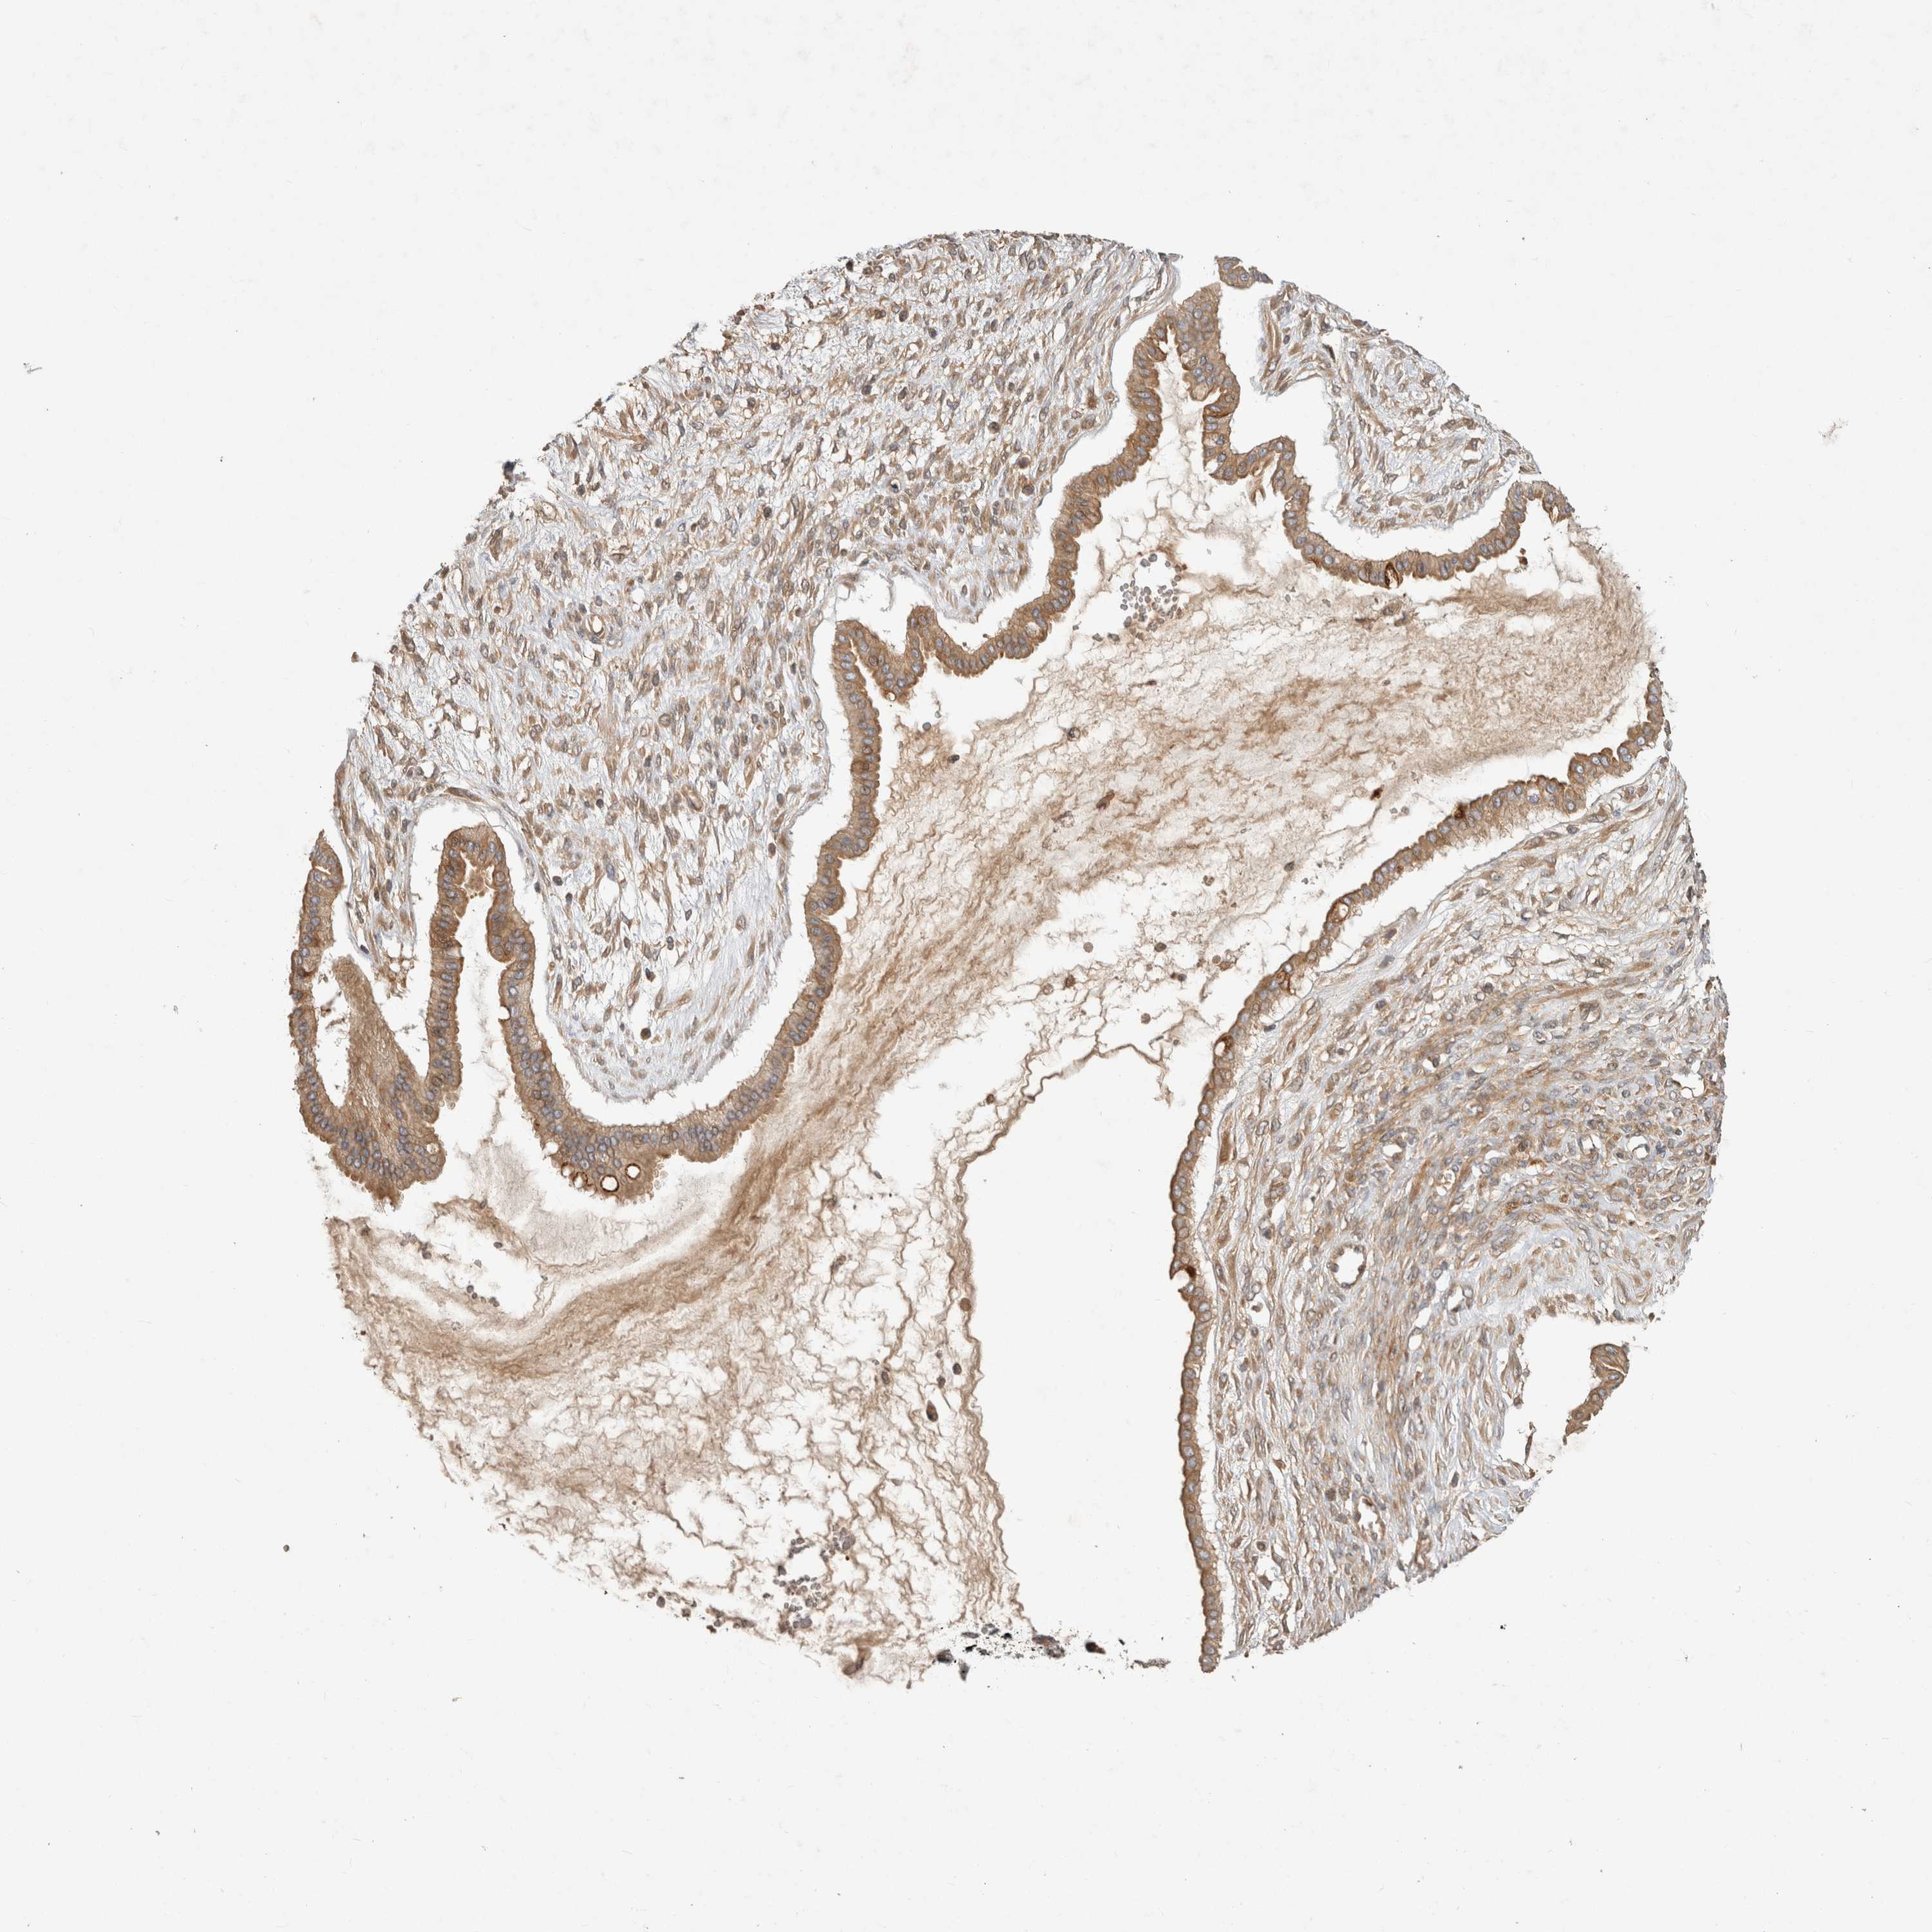

OVARIAN CANCER - Protein expressioni

A mouse-over function shows sample information and annotation data. Click on an image to view it in a full screen mode. Samples can be filtered based on level of antibody staining by selecting one or several of the following categories: high, medium, low and not detected. The assay and annotation is described here.

Note that samples used for immunohistochemistry by the Human Protein Atlas do not correspond to samples in the TCGA dataset.

Antibody stainingi

Antibody staining in the annotated cell types in the current human tissue is reported as not detected, low, medium, or high, based on conventional immunohistochemistry profiling in selected tissues. This score is based on the combination of the staining intensity and fraction of stained cells.

Each image is clickable and will lead to virtual microscopy that enables deeper exploration of all samples and also displays staining intensity scores, fraction scores and subcellular localization as well as patient and tissue information for each sample.

Antibody HPA024313

Antibody HPA027983

Antibody HPA028628

Staining

High

Medium

Low

Not detected

Intensity

Strong

Moderate

Weak

Negative

Quantity

>75%

75%-25%

<25%

None

Location

Nuclear

Cytoplasmic/membranous

Cytoplasmic/membranous,nuclear

Carcinoma, endometroid